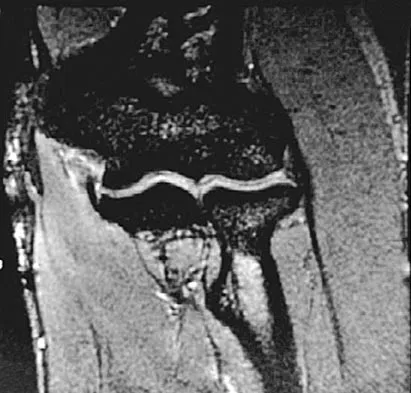

A 35-year-old woman dislocated her right shoulder in a fall from a step stool several months ago. She now reports several painful recurrences. Examination reveals anterior and inferior apprehension that reproduces her symptoms. An MRI scan is shown in Figure 17. Management should consist of